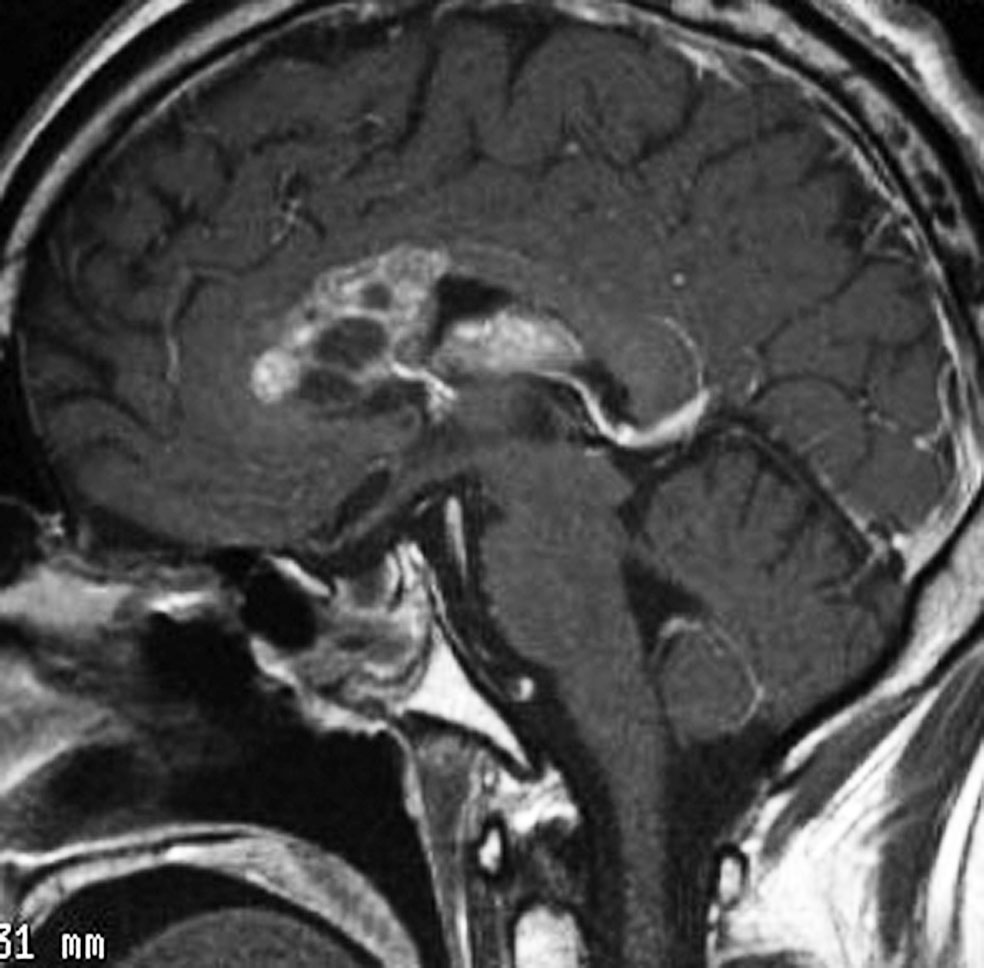

20歳くらいから尿崩症があり,2年後に汎下垂体機能低下症と軽度の認知機能低下を生じました。脳室壁と松果体,神経下垂体にジャーミノーマが広がっているのですが,脊髄背面と脳幹部の周囲にも腫瘍結節が見られました。脳室上衣以外の部位に腫瘍があるので,播種を疑いました。ジャーミノーマの播種というのは実際にはとても珍しくてなかなかみないものです。HCGは軽度の上昇,鼻孔から下垂体部分を生検して病理確定診断して,化学療法と脳脊髄照射 25.2Gy をしました。腫瘍は1コース目の化学療法でほとんど消失したので,他の組織型の悪性混合性胚細胞腫瘍ではないと考えられます。

3年後に脳室壁に再発しました。脳梁と脳弓の機能低下があり認知機能低下は高度でした。松果体と神経下垂体には再発はありません。

この再発の原因には,側脳室前角の先端部が照射野に十分含まれなかったという疑念があります。